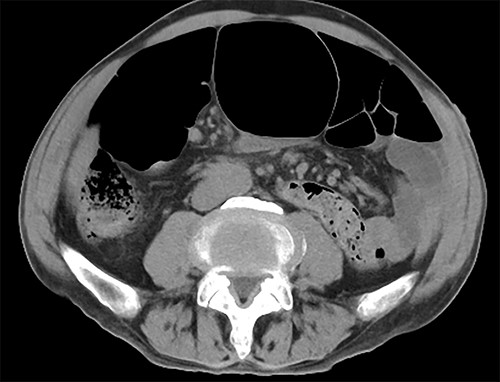

The sigmoid colon was elongated, and a scar was detected near the SD junction, which appeared to be a site of repeated torsion (Fig. 4). Dilation of the sigmoid colon revealed no inflammation on the serosal surface. The laparoscopic procedure was completed after confirming that the sigmoid colon was sufficiently elevated to the left lower abdomen. A 4-cm cross incision was made at the opposite of McBurney’s point, and the sigmoid colon was raised outside the wound (Fig. 5). The intestine was considered to be sufficiently decompressed to allow anastomosis. The intestinal tract was separated, and anastomotic reconstruction was performed using functional end-to-end anastomosis. The operation duration was 89 min, and the bleeding amount was 5 ml.

Surgical findings. Sigmoid colon was elongated and there was scar near the SD junction.